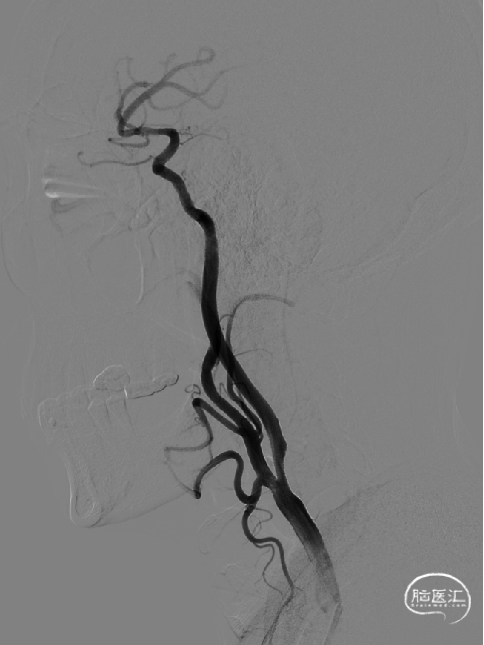

以260cm泥鳅导丝辅助125cm Simmons 2和6F导引导管超选右侧颈总动脉远端,撤出泥鳅导丝及造影管,再次造影可见右侧颈内动脉起始部重度狭窄,狭窄率约80%。

术后侧位造影: